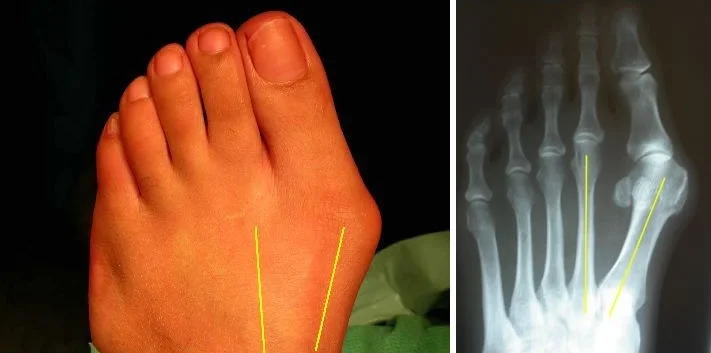

Metatarsus primus varus:

- Congenital, or

- Geriatric

Radiology - Hallux Valgus

- XR views:

- AP standing:

- Lateral deviation of big toe

- Increased varus of 1st MT

- Subluxation of MT-Phal. joint